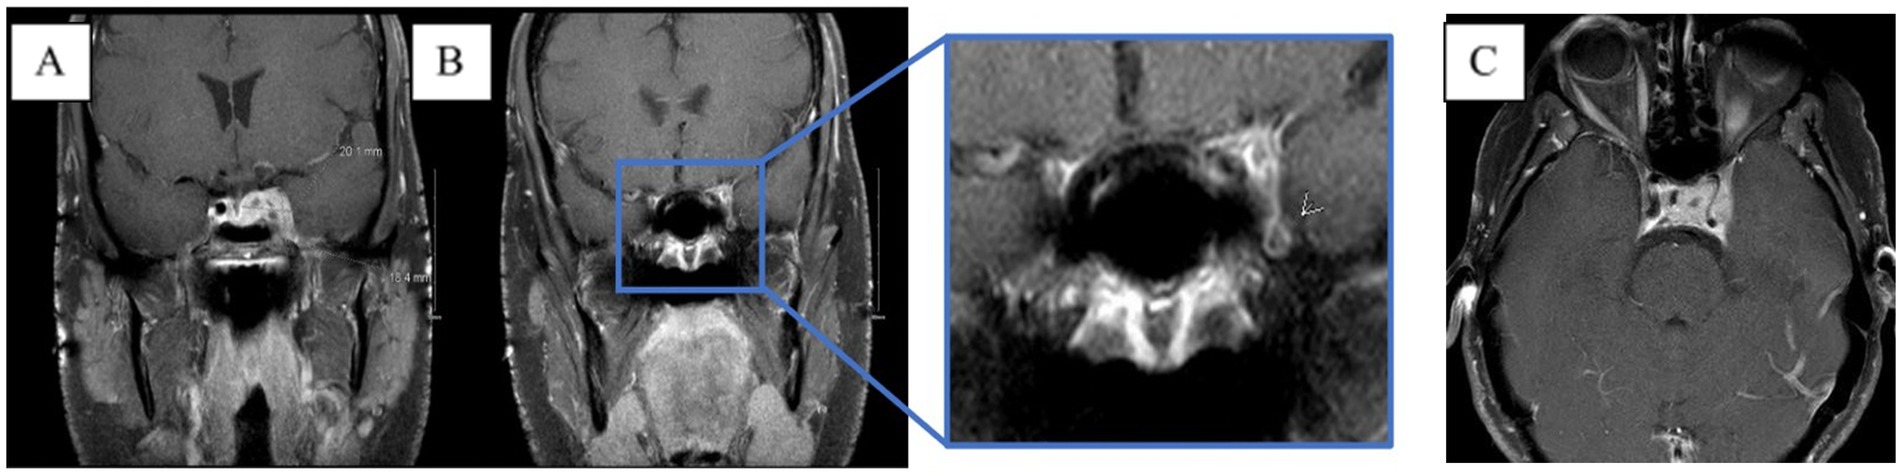

Table 1. CSF values over the disease course, starting from initial presentation to hospitalization 3 months later.

Moreover, 13 weeks after the initial presentation, he returned to the ED with altered mental status and was admitted for evaluation. On examination, he demonstrated word-finding difficulties, impaired attention, and neck stiffness. No other focal signs were noted. MRI re-imaging demonstrated new leptomeningeal enhancement and acute strokes of the bilateral basal ganglia, hypothalamus, and medial temporal lobes, with vascular imaging demonstrating multifocal stenoses with bilateral ICA involvement (Figure 2). The CSF studies revealed significant neutrophilic pleocytosis with an elevated white blood cell count (WBC) of 3,089 uL (72% polymorphonuclear neutrophils (PMNs)), hypoglycorrhachia (35 mg/dL), and elevated protein (124 mg/dL; Table 1). Infectious workup, including bacterial, fungal, and acid-fast cultures; BioFire Meningitis/Encephalitis PCR panel; Nocardia cultures; cryptococcal antigen; and Toxoplasma PCR, was negative. Broad-spectrum antimicrobials, including vancomycin, ceftriaxone, ampicillin, acyclovir, and amphotericin, were initiated for empiric meningitis coverage, covering typical and atypical bacterial, viral, and fungal meningitides in the setting of a seemingly indolent course. Ampicillin and acyclovir were quickly discontinued due to negative testing. The patient was tapered off outpatient steroids during hospitalization. Despite serial CSF studies showing an improving cell count (Table 1), symptoms continued to worsen, leading to a comatose state, which resulted in the patient being intubated and transferred to the intensive care unit on hospital day 3. Serial imaging showed new and expanding regions of diffusion restriction involving the basilar artery territory, as well as proximal posterior cerebral artery stenosis presumably secondary to vasospasm (Figure 3). Magnetic resonance angiography of the head showed enhancement around the basilar artery, raising concern for infectious vasculitis.